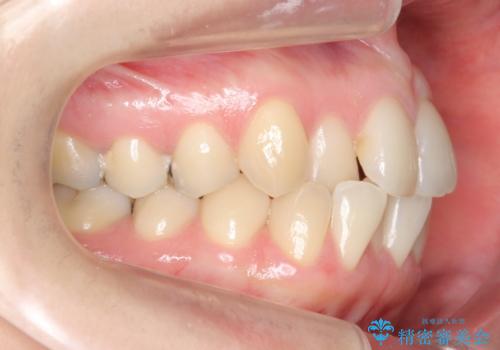

上の前歯が一部引っ込んでいる 下のがたがた マウスピース矯正

- 前歯2本が後ろに引っ込んでいる状態でした。

マウスピースで歯を抜かずに矯正しました。

かみしめがある方は、奥歯のかみ合わせが弱くなることがマウスピース矯正の欠点ですが、装着時間や時間帯を工夫して奥歯もしっかりかんだ状態で矯正終了をしています。